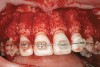

Fig 18 (through Fig 21). Note lack of alveolar development from congenitally missing Nos. 24 and 25. Surgical procedures after 5 months of orthodontic alignment included single-tooth osteotomies Nos. 6 to 11 and Nos. 21 to 28 and buccal corticotomies on all other teeth. Anchorage plate was stabilized to piriform rim.

Figure 18

Fig 20. Note lack of alveolar development from congenitally missing Nos. 24 and 25. Surgical procedures after 5 months of orthodontic alignment included single-tooth osteotomies Nos. 6 to 11 and Nos. 21 to 28 and buccal corticotomies on all other teeth. Anchorage plate was stabilized to piriform rim.

Figure 20

Fig 21 (and Fig 20). There is significant lateral dentoalveolar expansion of arches and alveoloskeletal correction in maxillary and mandibular anterior regions. Alveolar bone volume was increased in lower anterior to create optimal implant sites and establish ideal interincisal function and stability.

Figure 21